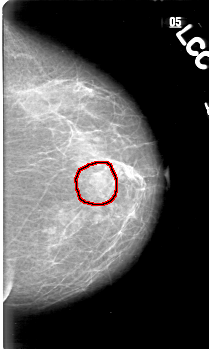

D_4033_1.LEFT_CC

FILE: D_4033_1.LEFT_CC.OVERLAY

TOTAL_ABNORMALITIES 1

ABNORMALITY 1

LESION_TYPE MASS SHAPE IRREGULAR MARGINS ILL_DEFINED

ASSESSMENT 0

SUBTLETY 5

PATHOLOGY BENIGN

TOTAL_OUTLINES 1

BOUNDARY